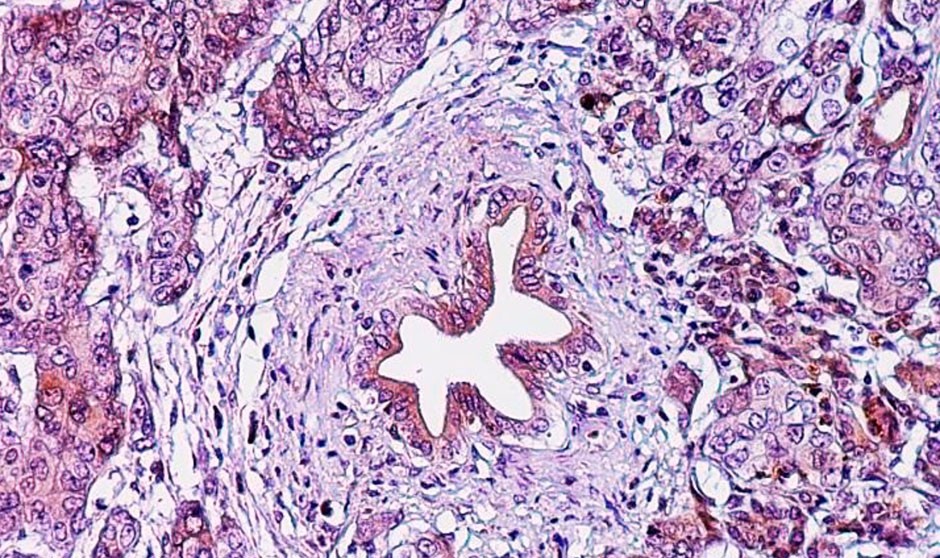

Las muestras tumorales estudiadas en la rama reciente también presentaban cantidades mucho mayores de células inmunitarias anticancerosas que las muestras de pacientes a los que se administró solo la vacuna o la vacuna más nivolumab.